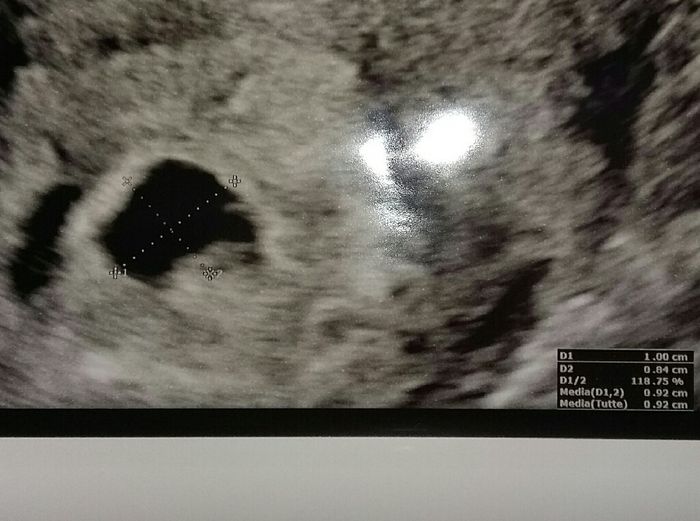

Mamma Marzo 2020....

Da Valentina , Il 26 Luglio 2019 alle 21:20

Mi sa che sono la prima!!! la mia dpp è 5 marzo.... oggi sono a 4+5 .... ho qualche crampetto basso ventre ogni tanto.... poca fame ( cosa strana per me visto che di...